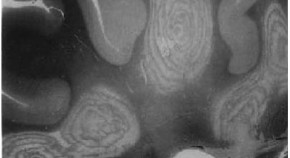

• Small-fiber neuropathy is a condition that has been underdiagnosed in the past, partly because small nerve fibers cannot be observed using routine neurophysiological tests. Skin biopsy is a safe, minimally invasive tool that can provide important diagnostic information on small nerve fibers, and in this article Lauria and Devigili discuss how this approach is being applied to the diagnosis and monitoring of peripheral neuropathies.

• Giuseppe Lauria

• Grazia Devigili

Review Article